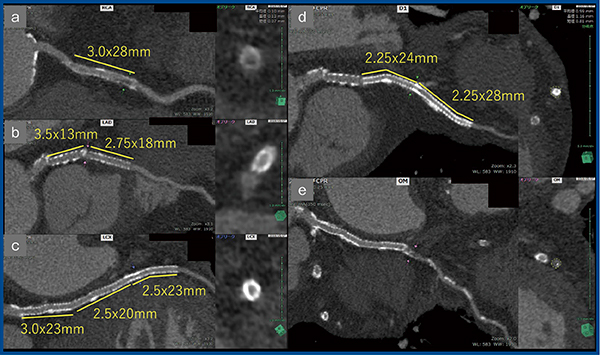

症例1は,87歳,男性,2007年から5回のPCIが施行され,冠動脈内に計8本のステントが留置されている。労作時の息切れを主訴に,当センターで冠動脈CTとCAGを行った。冠動脈CTでは,右冠動脈(RCA)の3.0mmステント内に狭窄を疑う陰影が認められるが(図4 a),LADと左回旋枝(LCX)のステントには有意な所見は認められない(図4 b,c)。左前下行枝から分岐する対角枝(D1)にも2.25mmのステント2本が留置されており(図4 d),鈍角枝(OM)は末梢では評価が難しい(図4 e)。CAGではRCAは狭窄ではなく,CTでの狭窄はアーチファクトだと考えられた。OMについては,わずかに狭窄が見られたが冠血流予備量比(FFR)を調べたところ虚血なしとされ,薬物治療となった。

図4 症例1:ステント内再狭窄疑い